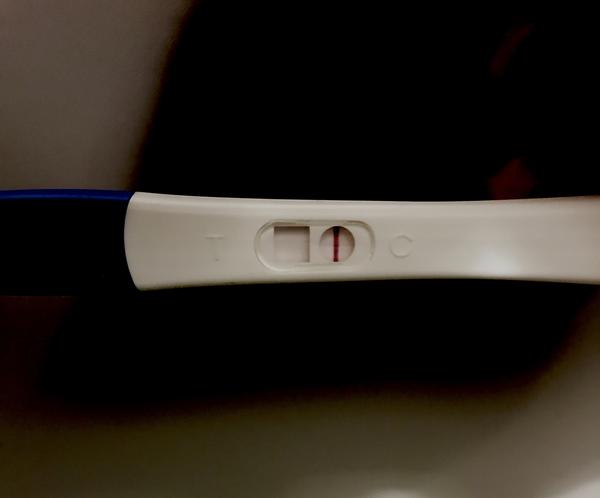

@wewe28 ahojky, to iste ako minuly týždeň, slabý ružový duch na 25kovom teste, na 10kovom ani náznak, cecky už o číslo väčšie ako zvyčajne, ráno nevoľnosť ako hovado, biely hustý výtok bez zápachu, fakt tomu nechápem... no a keď berieme od spinenia je to 13 dni, keď to berieme že to bola MS (čo podľa mna nebola) tak 13 DC, zajtra začínam poslednú krabičku Duphastonu a potom kontrola u gynekológa..prikladám fotky ale nemyslím si že to na mobile vidno, je to viac vidno voľným okom aj po rozobratí ale cez mobil nie. Španielska dedina toto, ale asi sa na to vykaslem len ide Silvester a neviem či si teraz dať pozor s alkoholom alebo nie

No nič tam nieje vidno ale ! Ak si tehotná druha čiarka silnie tak počkaj a správ si test neskoršie 🙂

@wewe28 však práve, že to by som bola riadne na hlavu pokladať to spinenie za MS nakoľko to nič nebolo...ešte ma napadlo ako som tu čítala že niektorým neukázal tehu test do 8-9 týždňov 2 čiarky čo by vysvetľovalo moju situáciu ale to by bolo už plne fantázie takze to neberiem ani do úvahy, možno sa mi búria hormóny, kto vie prečo tie nevoľnosti a plne cecky apod 😂 gynekológ neordinuje medzi sviatkami, takze krv vylúčená...ale muž ma “prekvapil” dvoma testami (chudák nevedel čo kupuje, sú to 25ky) ktoré si MUSÍM zobrať na chatu a testnut na Silvestra, ale povedala som mu, že nech s tým konečne prestane a nič na tom teste nie je a koniec, ideme ďalej...a na Silvestra budem toľko piť, koľko mi povie telo - lebo ak som aj tehotná (fantazírujme) tak si telo aj tak povie nevoľnosťami...iné ma nenapadá, svet sa nezrúti 🙂